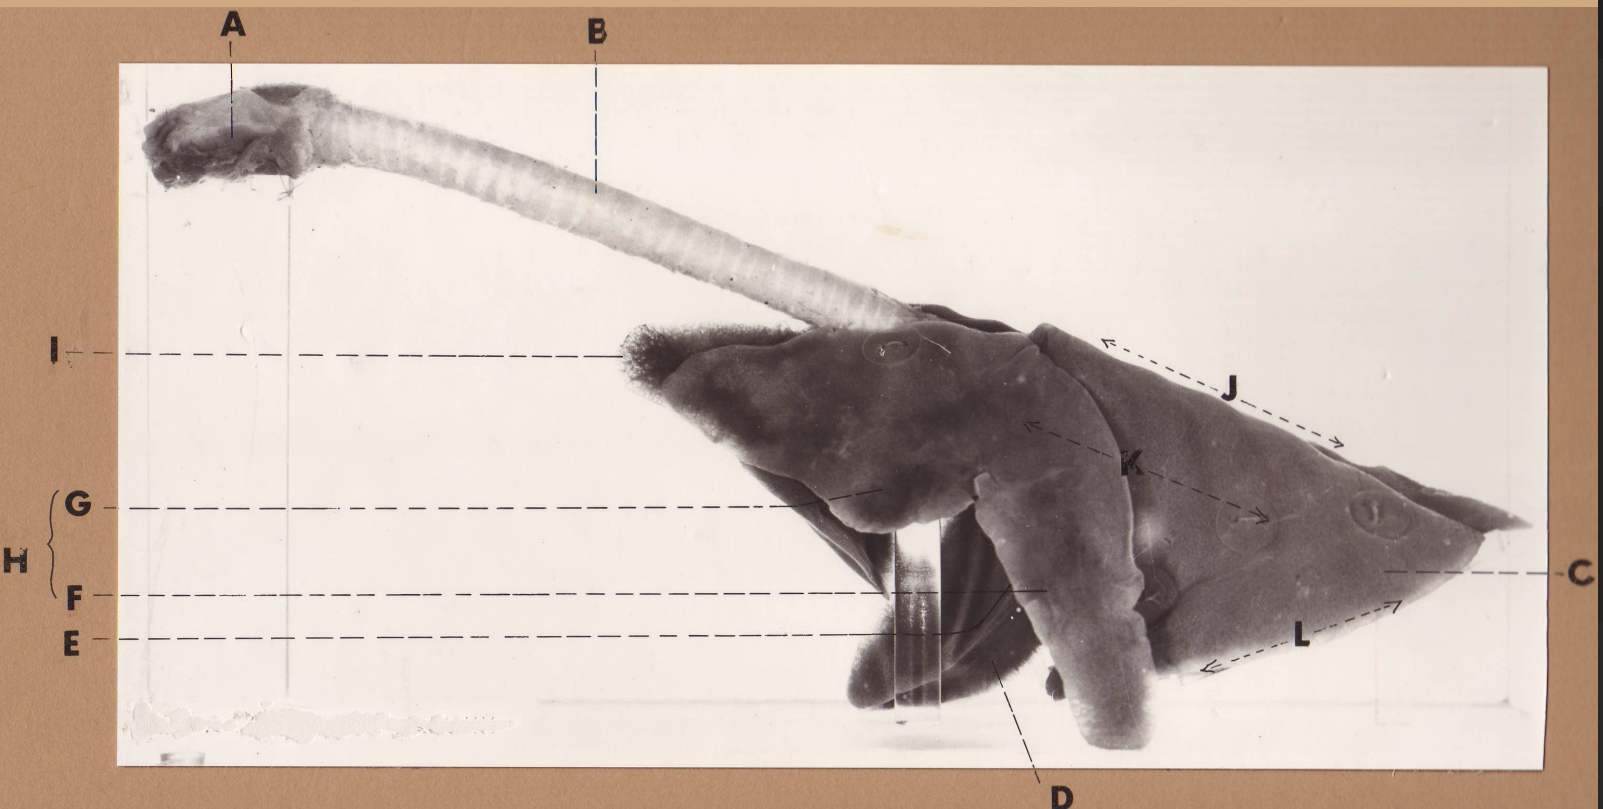

A

(cat larynx/trachea/lungs, L lateral)

larynx

B

(cat larynx/trachea/lungs, L lateral)

trachea

C

(cat larynx/trachea/lungs, L lateral)

caudal lobe

D

(cat larynx/trachea/lungs, L lateral)

middle lobe

E

(cat larynx/trachea/lungs, L lateral)

cardiac notch

F

(cat larynx/trachea/lungs, L lateral)

caudal segment, cranial lobe

G

(cat larynx/trachea/lungs, L lateral)

cranial segment, cranial lobe

H

(cat larynx/trachea/lungs, L lateral)

cranial lobe

I

(cat larynx/trachea/lungs, L lateral)

apex

J

(cat larynx/trachea/lungs, L lateral)

dorsal border

K

(cat larynx/trachea/lungs, L lateral)

costal surface

L

(cat larynx/trachea/lungs, L lateral)

basal border